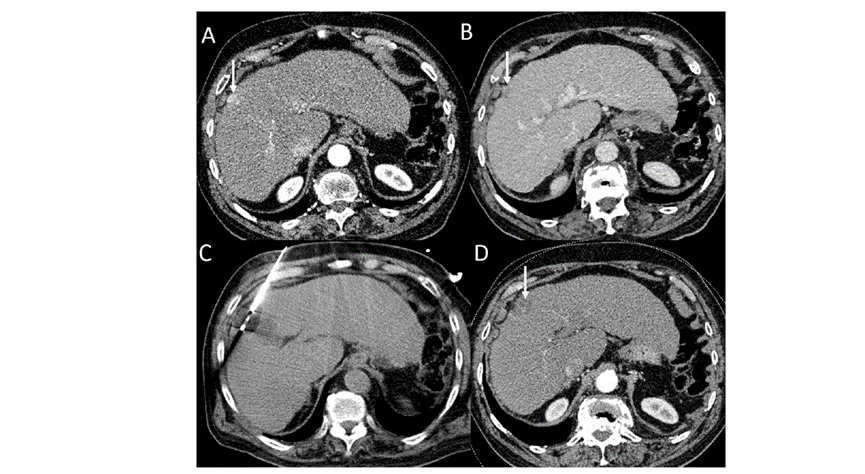

79 岁男性,肝转移(结直肠癌)肿瘤的完全消融病例

( a ) 轴向 MRI 和 ( b ) 轴向 CT 显示肝S8段有一个16mm的病灶,邻近肝缘。

( c )冷冻消融期间CT显示放置了2个冷冻探针,低密度冰球包围病灶。

(d)术后1个月随访 CT显示冰球对应的坏死区域,未见复发。

(e)术后6个月的CT,坏死区域缩小,未见复发。

(f)与基线影像(g)相比,12个月后的FDG-PET/CT显示未见FDG摄取。

62岁女性,肝转移(卵巢癌)肿瘤的完全消融病例

(a)轴向CT显示病变位置毗邻心脏和上腔静脉(黑色箭头)。

(b)术中轴向CT扫描:使用三个冷冻探针。

(c)冠状面和(d)矢状面显示冰球毗邻心包。

1个月后的轴向(e)和冠状位(f)增强CT扫描显示低密度区域,由于肉芽组织反应引起的边缘增强。